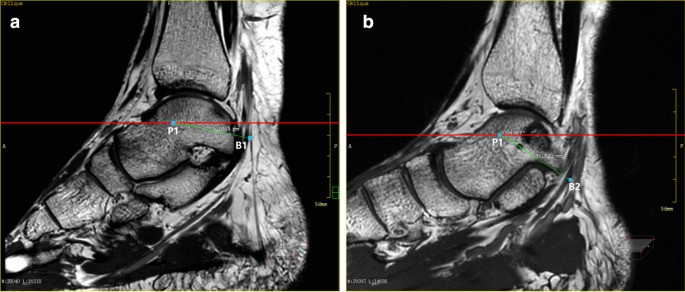

Image reformation method

The relative position of the ankle canal reference line l and the medial and lateral nerve: a a schematic diagram showing two projection lines,P1 is projection of the lowest point of the medial malleolus and P2 is projection of the calcaneal tuberosity on the sagittal image; b the relative position of the bifurcation point and Line 1 and Line 2 on the sagittal image through the bifurcation point of the medial and lateral nerves of the plantar; c measure the distance between the bifurcation point and P1 and the angle between the bifurcation point and Line 1 on the sagittal image passing through the bifurcation points of the plantar and lateral nerves

Measurement of the relative position of the medial and inferior calcaneal nerve on the sagittal plane: a measure the distance between the bifurcation point of MCN (B1) and projection of the lowest point of the medial malleolus (P1) and the angle between the bifurcation point and Line1; b the distance between the bifurcation point of ICN (B2) and P1, and the angle between the bifurcation point and Line 1 are measured